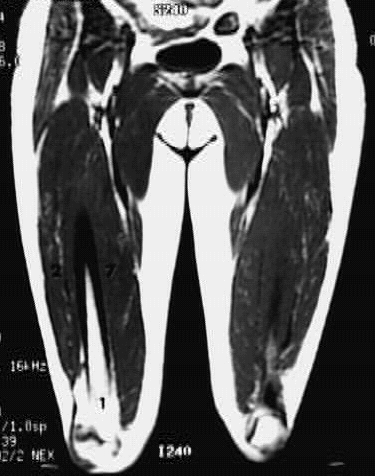

Lower Limbs: Thigh Coronal Zoom 1 of 3